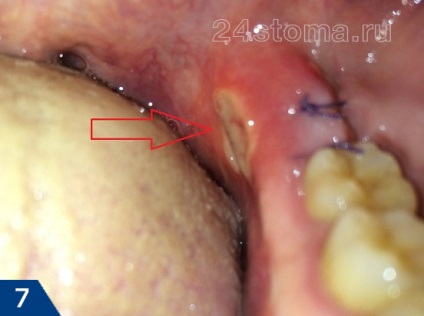

Gumele după înțelepciunea extracție dentară (OK) -

Când îndepărtați molarilor de minte sunt aproape întotdeauna închise cu copci. Acest lucru este necesar deoarece Acești dinți sunt în țesuturile moi și adâncimea la această locație este mucoasa foarte mobil. Nu există cusături în această situație poate duce la pierderea de cheag si inflamatia. Dar, în cazul în care pacientul are o lungime mare a spațiului suficient maxilarului și dinte înțelepciune - Hole va arăta în mod tradițional (Figura 3).